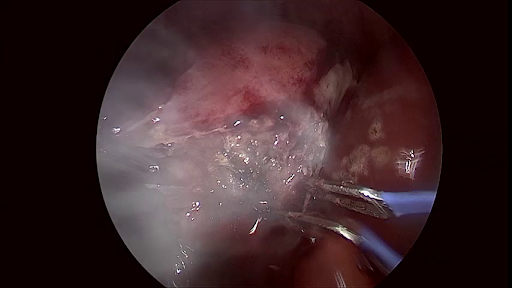

(a) Similarity of frames within different surgery types

Figure 5: Challenges associated with Laparo425 dataset